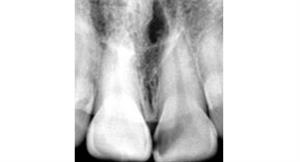

Root Canal Treatment

After

A root canal procedure (endodontic treatment) is often required to save an infected tooth. Bacteria can enter a tooth through a cavity or a damaged filling. When this happens, the tooth can become abscessed, meaning the pulp inside the tooth becomes infected. An abscessed tooth can be quite painful and cause swelling in the surrounding gum tissues. If left untreated, it can cause several oral health problems. A root canal procedure removes the infected pulp and any other infected tissues within the tooth.